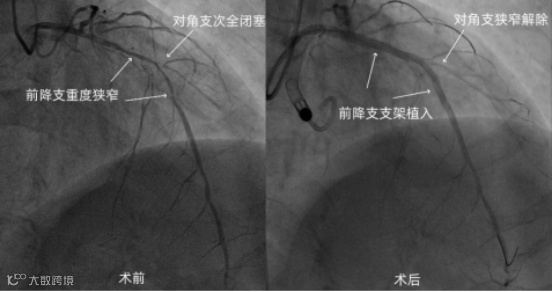

入院后考虑患者缺血性心肌病可能性大,遂行冠脉造影,结果显示冠脉三支病变,左主干末端70%狭窄伴钙化,前降支开口-中段弥漫性钙化性病变,前降支最重90%狭窄,对角支次全闭塞,回旋支近段80%狭窄,右冠中段70%狭窄,后降支慢性完全性闭塞。

经分析,患者需行冠脉血运重建治疗,但患者病情复杂,手术风险极高。杨人强主任立即组织病例讨论,考虑患者外科手术风险极高,建议行PCI术。但患者心功能差、病变复杂、手术难度大,术中出现血流动力学异常风险高,为有效维持术中血流动力学稳定,拟在机械循环辅助装置支持下行PCI术。经充分跟患者家属沟通后,治疗团队于PCI术前经患者右侧股动脉预先送入 SynFlow3.0 提供心室辅助。

术中,SynFlow3.0 将患者左心室内的血液通过血流通道泵入主动脉中,实现对左心室的辅助泵血,增加了循环支持,保证了全身重要器官的循环灌注,术中患者心率、血压、血氧饱和度等各项生命体征平稳,整个手术持续 3 小时,最终成功实现冠脉完全血运重建。患者术后恢复良好,已康复出院。

高危PCI手术操作复杂、手术时间更长,保证患者术中血流动力学的稳定,是手术成功及影响预后的关键。经皮心室辅助装置维持了稳定的血流动力学状态,取得了出色的冠脉血运重建效果。